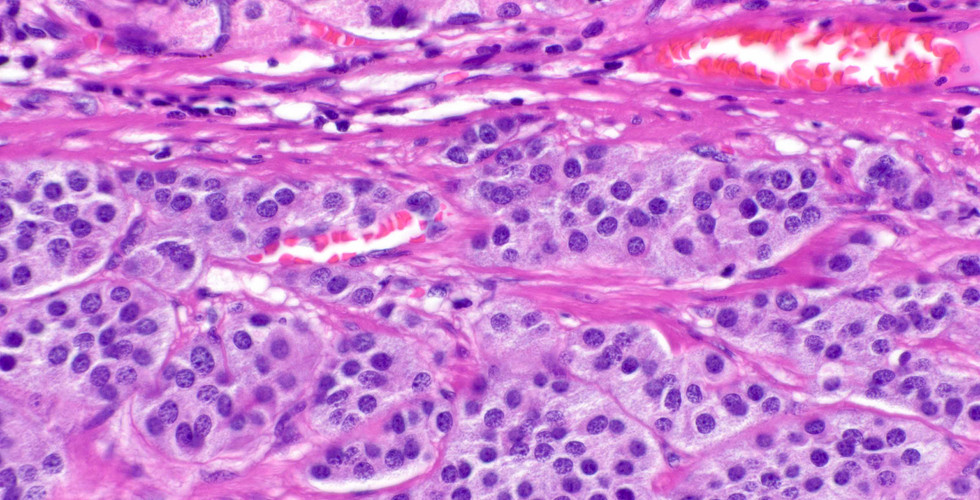

Well differentiated neuroendocrine (carcinoid) tumor, the old Type 3, arising in normal oxyntic mucosa, which is more aggressive than those associated with autoimmune gastritis (Type 1). However, a pitfall on mucosal biopsies is that mucosa on top of the lesion can display atrophic features. This is yet another reason to remind our endoscopy colleagues to be in the habit of sampling flat mucosa around gastric lesions.